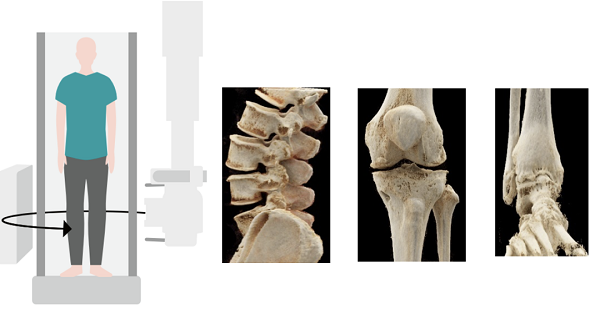

Multitom-Rax 双悬吊动态多功能DR到底有何独到之处,让其超越一众DR,成为价格之王?根据西门子Multitom-Rax装机医院使用反馈来看,Multitom-Rax主要价值是其具备的立位3D扫描技术。Multitom-Rax悬吊动态DR,能够完成200°的广角扫描,同时具备高DQE和低剂量的技术特点。在三维影像的清晰度处理上,Multitom-Rax悬吊动态DR可以完成0.25mm空间分辨率影像重建,支持包括全CT功能分析,包括:MPR多平面重建技术、MIP密度投影重建技术和VRT(3D)技术,在三维影像重建技术上与CT无异,支持MAR金属伪影去除。在立位下可以对相关腰椎疾病、膝关节疾病以及踝关节疾病,进行更加精准的评估分析。

由于人体骨骼在承重与非承重状态下所承受的压力不同,关节间隙的差异在站卧之间可达数倍。CBCT平板和球管围绕患者进行等中心旋转,可实现任意体位的锥形束CT扫描,在脊柱、关节、骨骼获取传统CT检查无法企及的承重位三维图像,真实反映骨骼受力情况并找到病症根源。它引领了立位3D检查的最新方向,精确地对关节力线进行评估,是外科手术成功与远期效果评估的重要因素。

可以说,西门子医疗Multitom Rax创造了立位3D检查的新纪元。它是第一台可以在人自然站立状态下,获得承重位的颈椎、腰椎、膝关节、踝关节的真实三维图像的锥形束CT。通过承重位呈现出的三维图像,它能够真实反映患者畸变部位的严重程度并找到疼痛根源,借助前所未有的诊疗新模式,为临床提供见所未见的站立位新视角。